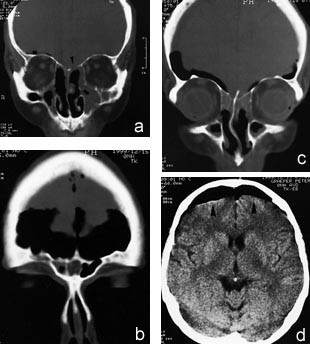

Pasienten gjennomgikk så evulsio samt endonasal etmoidektomi og antrostomi bilateralt i narkose. Det ble peroperativt bemerket noe aderent concha media på høyre side og noe uoversiktlige forhold, muligens etter tidligere operasjon. Det oppstod en arteriell blødning fortil i etmoidaltaket, som stanset etter komprimering over noen minutter med en adrenalintampong. Ingen øvrige komplikasjoner ble observert i det videre forløp, og pasientens umiddelbare postoperative tilstand var upåfallende. Neste dag utviklet han så en global hodepine som ble forverret ved forsøk på oppreist stilling. 3. postoperative døgn klaget han over rennende nese når han bøyde seg fremover. Han var preget av meningeal irritasjon, men man fant ingen reell nakkestivhet. Penicillin intravenøst ble administrert og man tok prøver av væsken til beta-2-transferrin-undersøkelse. Ny cerebral CT viste betydelige mengder luft i subaraknoidalrommet samt en ca. 5 mm stor defekt i skallebasis, lokalisert til etmoidaltaket på venstre side (fig 2). Ved ny skopi med 0˚ optikk fant man ingen pågående lekkasje. Blodprøvene viste maksimal CRP-stigning til 47, leukocytter 11,3, normale elektrolytter og kreatinin. Beta-2-transferrin-elektroforesen var positiv, hvilket indikerte lekkasje av spinalvæske. Pasienten ble observert kontinuerlig, og ny CT, som ble tatt 13 dager postoperativt, viste tydelig regresjon av den intrakraniale luften. Pasienten ble utskrevet i velbefinnende samme dag.

Ved avtalt kontroll ved poliklinikken sju uker etter operasjonen fant man ved CT ingen tegn til pneumocephalus. Pasienten hadde nå ingen nasalstenose eller rhinoré (fig 3).